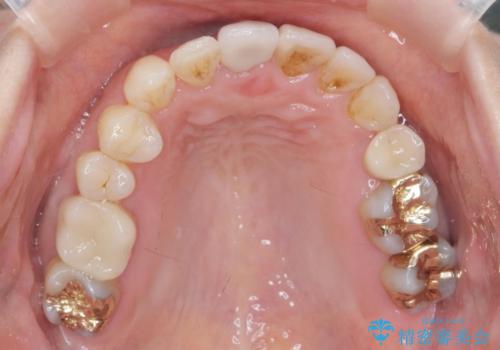

- 矯正や虫歯治療を終えた患者様です。

今後、詰め物や被せ物が歯軋りなどで割れないように、また歯のすり減りの防止のためナイトガードを作製しました。

ナイトガードは夜寝ている時に使用するものですがその時、矯正の後戻り防止の装置としても機能します。